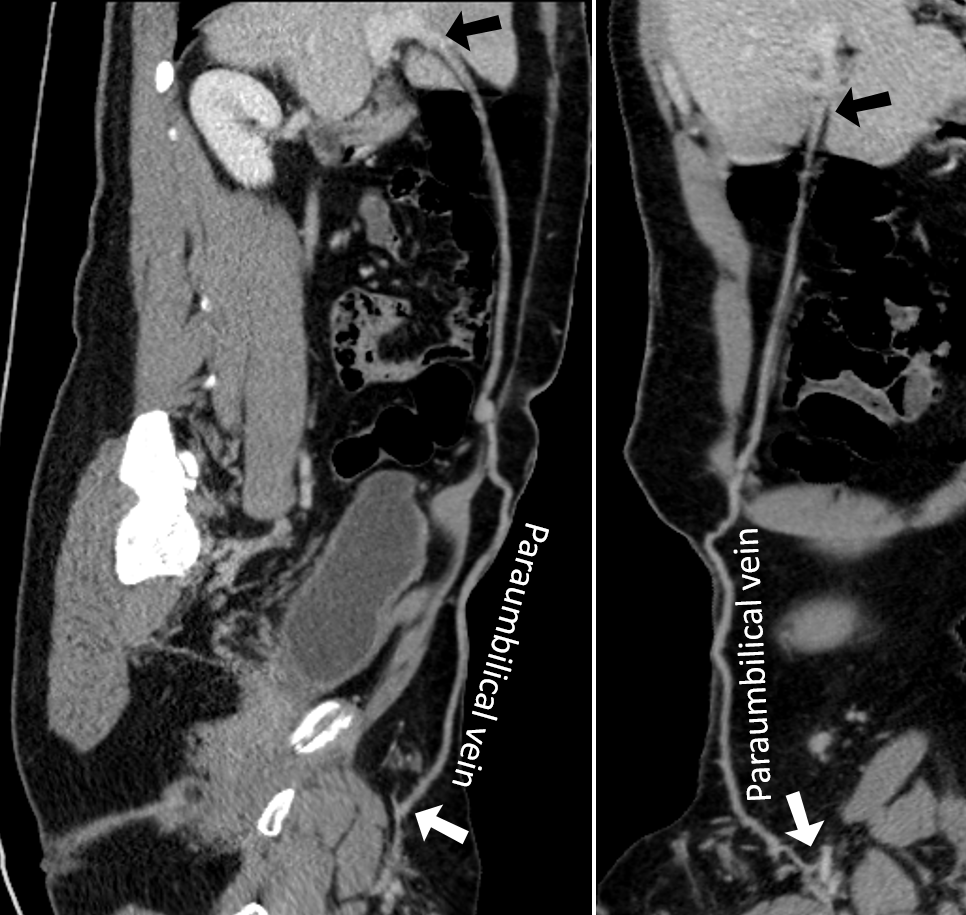

Interestingly, iNAV CE-MRA demonstrated dual inferior vena cava (IVC)- the left IVC was constituted from an azygos continuation into the vertebral venous plexus, and the right IVC had the anatomically correct connection with the right atrium. The right and left renal venous drainage was into right and left IVCs respectively (Fig 2). The pelvis and thigh station was beyond the MRA field of view. However, CTA additionally demonstrated paraumbilical venous collateralization between the superficial epigastric and hepatic portal veins (Fig 3). The iliofemoral venous system drained into the vertebral venous plexus and left IVC, while collateral tributaries from the lower extremity terminated into the paraumbilical vein and right IVC. Occlusive venous thrombosis of the external right iliac vein was identified and treated with staged thrombectomy and thrombolysis.

Fig 2- Demonstration of dual inferior venal cava anatomy using image-based navigator (iNAV) gadolinium enhanced MRA. (A) The azygos continuation joins the vertebral venous plexus (VVP), from which the left inferior vena cava (LIVC) originates. There is drainage of the left renal vein (LRV) into the LIVC. Inset- there is normal connection of the hemiazygos to the azygos vein. (B) Axial maximal intensity projection reformats demonstrate the relationship between the left renal artery (LRA), right renal artery (RRA), LIVC, and VVP. (C) The right renal vein (RRV) is a branch of the right inferior vena cava (RIVC), which terminates into the right atrium (RA). Notice continuation of the RIVC inferior to the origin of the RRV.  Fig 3- Twin curved multiplanar reformats from CTA imaging also demonstrated collateralization through the paraumbilical vein; proximal connection with the superficial epigastric vein (white arrow) and distal connection with the hepatic portal vein (black arrow).

Fig 3- Twin curved multiplanar reformats from CTA imaging also demonstrated collateralization through the paraumbilical vein; proximal connection with the superficial epigastric vein (white arrow) and distal connection with the hepatic portal vein (black arrow).